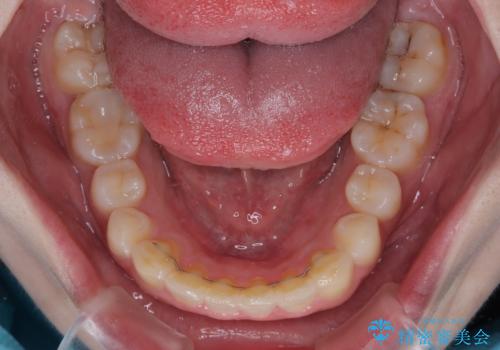

前歯のデコボコをインビザラインできれいに整える

- 前歯のデコボコと上下の隙間を気にして来院された患者様です。

前歯の捻れを改善するとともに、口元が少しでも引っ込むように治療計画を立て、仕上げることができました。